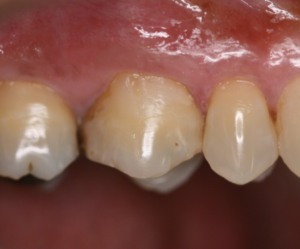

Vista inicial vestibular do elemento 16.